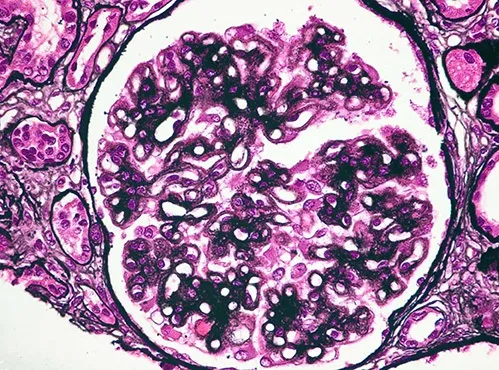

Diálise Peritoneal na Doença Renal Policística: existe algum motivo para não indicar?

Diálise Peritoneal na Doença Renal Policística: existe algum motivo para não indicar?

A DRPAD não é contraindicação à DP — e, na prática, muitos pacientes têm resultados comparáveis à hemodiálise. O “porém” está na mecânica: rins/hepatomegalia podem reduzir tolerância a volumes, aumentar risco de hérnias e extravasamentos, e piorar desconforto respiratório. Com técnica adequada (cateter presternal ou lateral, volumes menores, cicladora noturna e decúbito supino), a maioria das barreiras é contornável. Neste post, revisamos quando a DP é ótima, quando exigir cautela e como ajustar a prescrição para segurança e qualidade de vida.